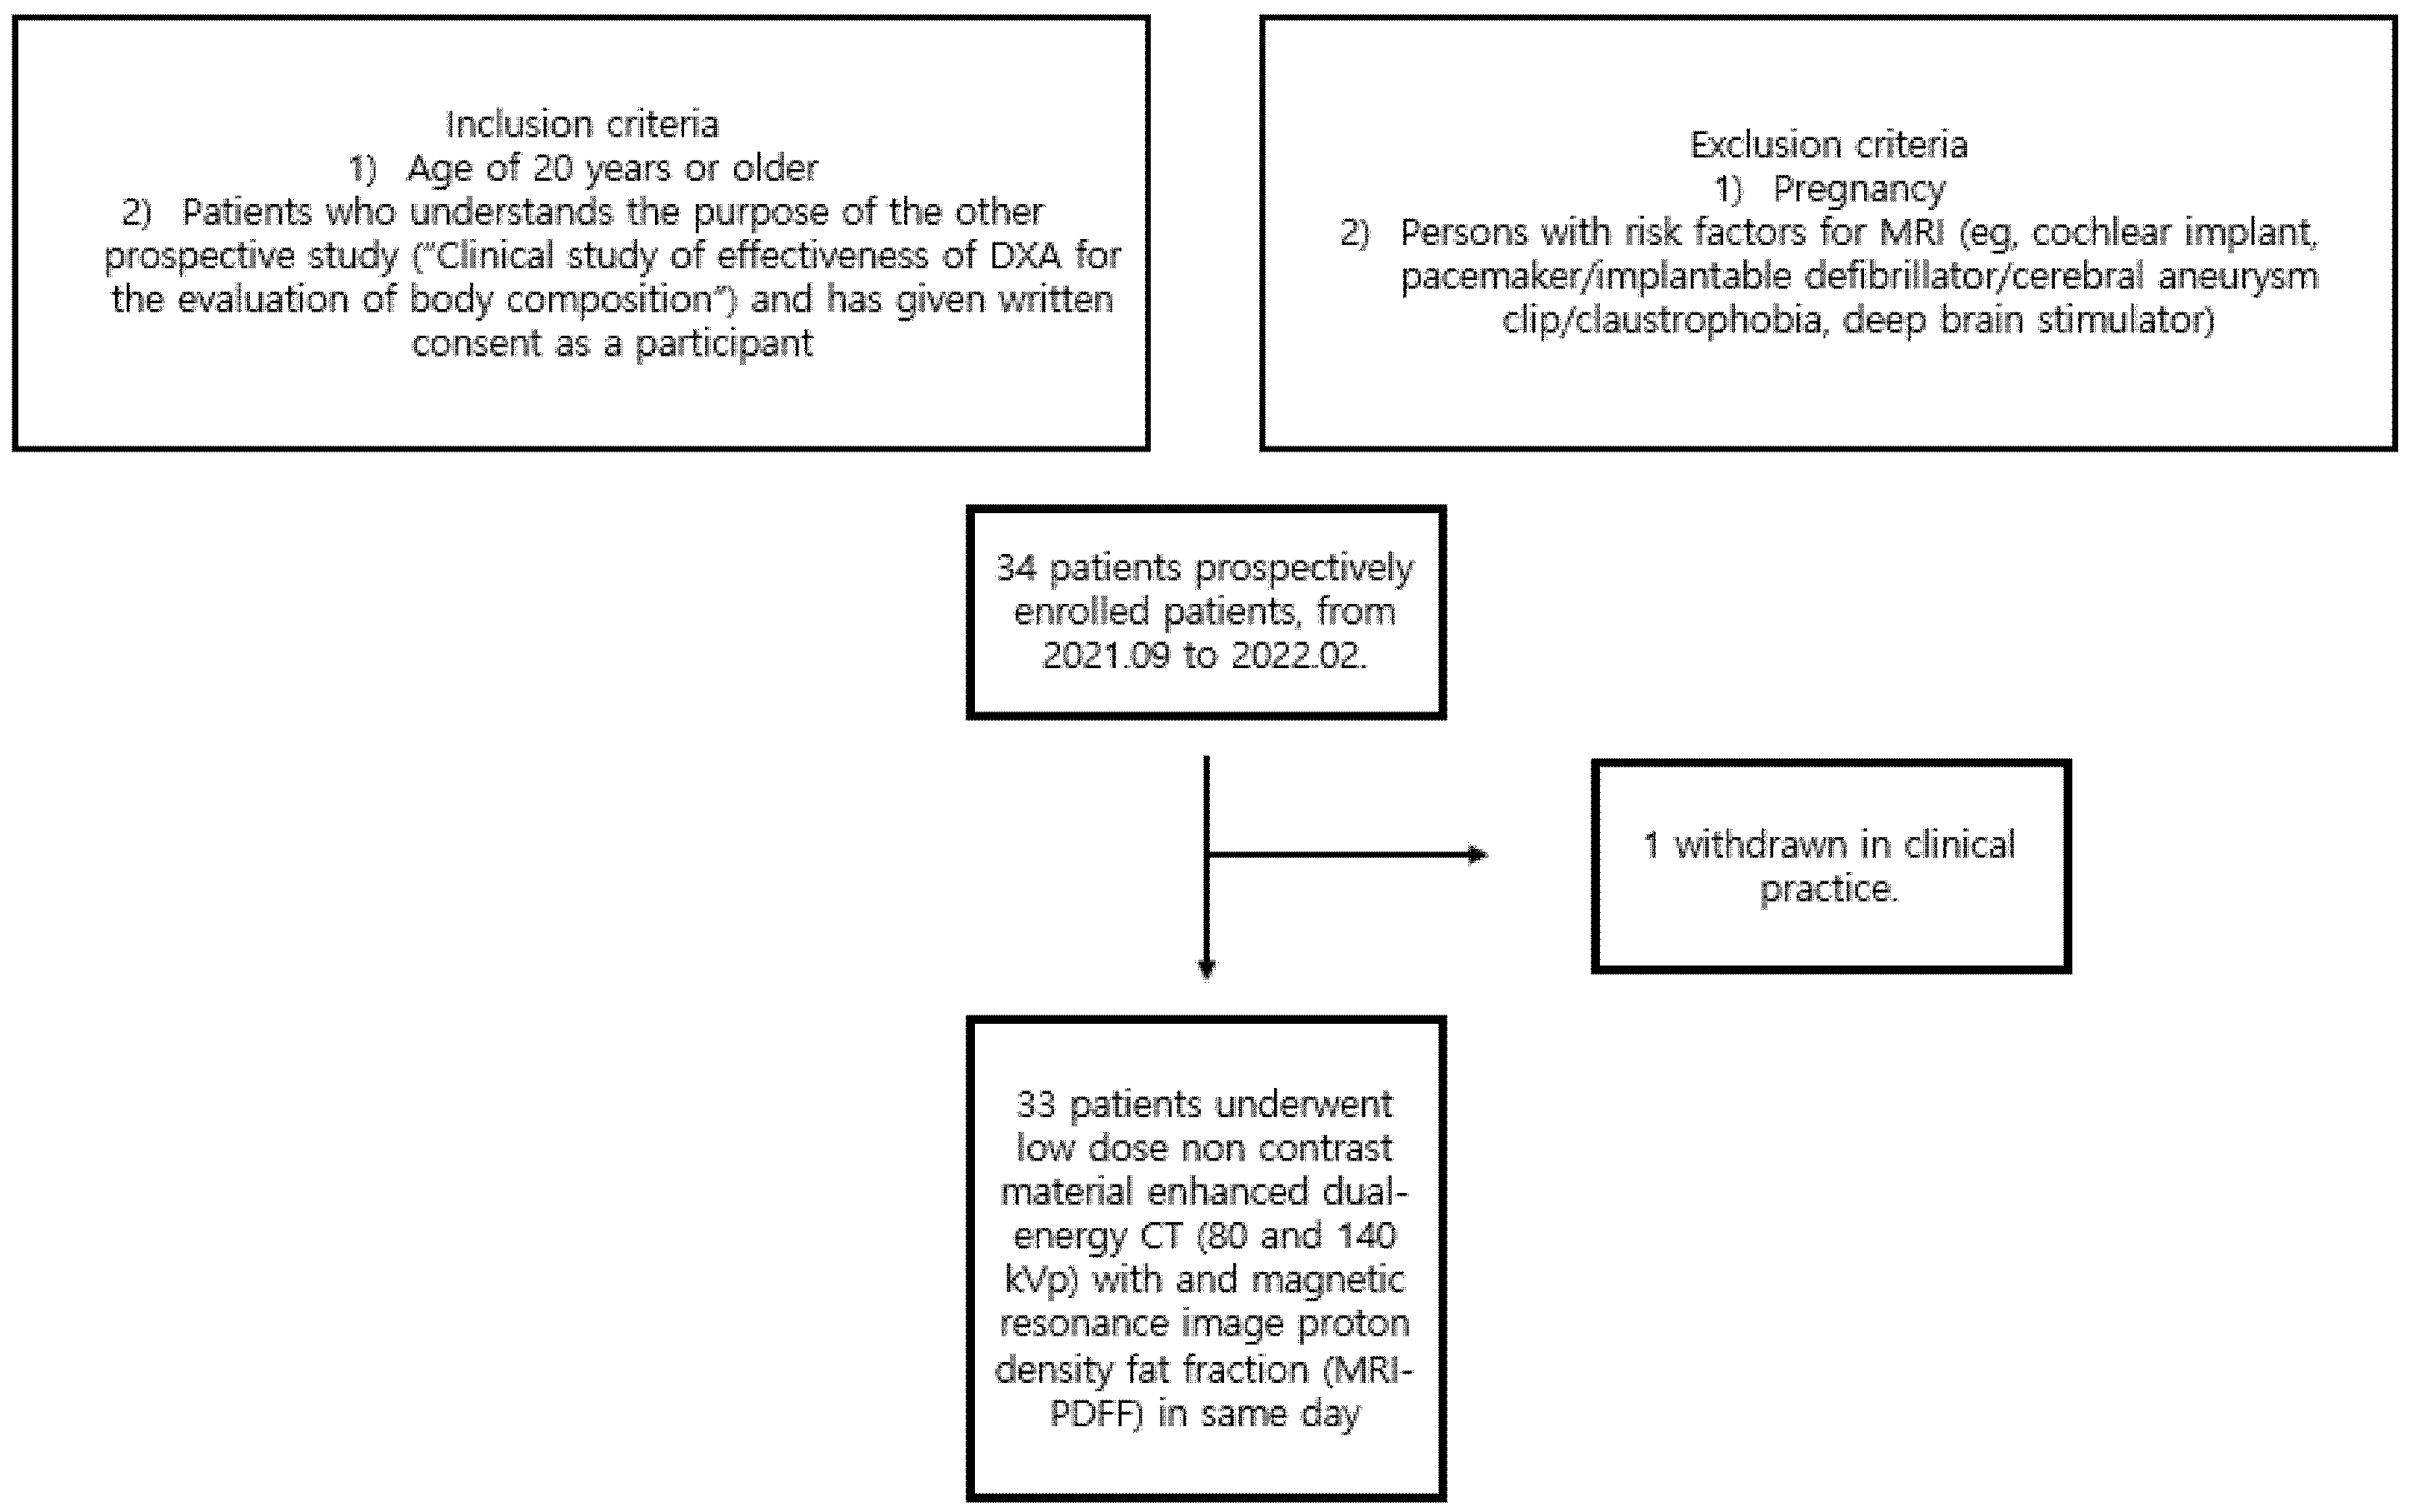

2. Materials and Methods

2.1. Patients